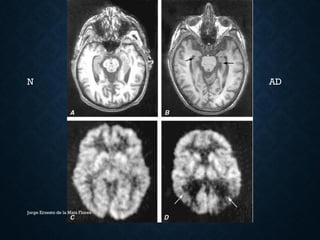

EXÁMENES AUXILIARES

• TAC/RM: Atrofia cortical posterior, temportal medial e

hipocampo.

• SPECT/PET: hipoperfusión/hipometabolismo corteza T-P

posterior, NAA, mioinositol

• LCR: A42;  hiperfosforilada (anciano normal)

N AD